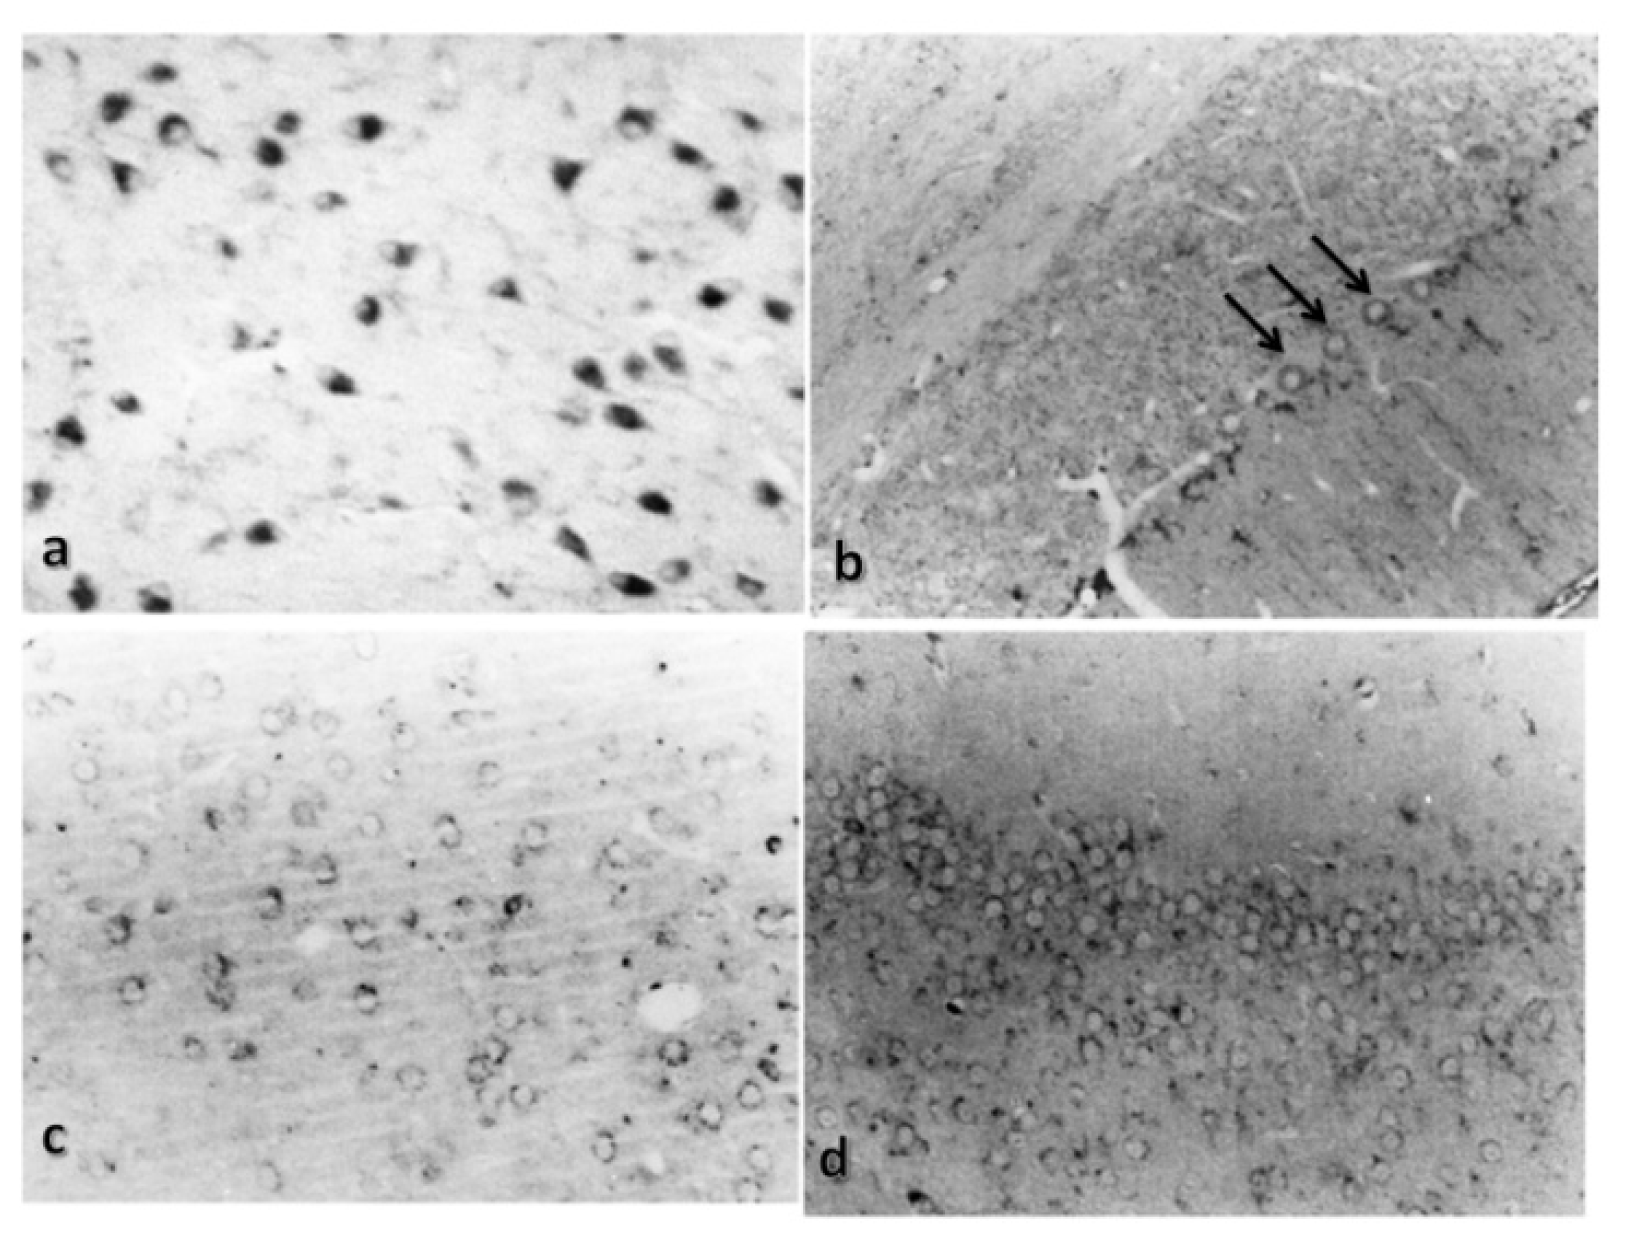

2.2. Basal Distribution of Cathepsin B and Cystatin C

2.3. Effect of TBI on Cathepsin B and Cystatin C Distribution